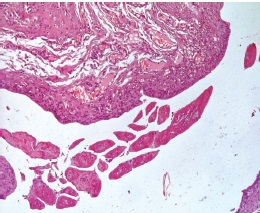

На 2-й нед. исследования при световой микроскопии гистологических образцов кожи области гетеротопической фиксации имплантата у животных между дермой и мышцей спины отмечали формирование толстостенной соединительнотканной капсулы со слабой инфильтрацией стенок макрофагами и мононуклеарными лейкоцитами. Между волокнами соединительной ткани выявили большое количество мелких тонкостенных кровеносных сосудов без признаков гемоциркуляторных нарушений. В просвете соединительнотканной капсулы сохранялись фрагменты имплантированных депротеинизированных губчатых костных матриц, представленные зрелой костной тканью. В тканях, перифокально области имплантации костных матриц, у животных формирования клеточно-воспалительного инфильтрата выявлено не было (рис. 3).

Рис. 3. Фрагмент кожи кролика линии NZW, 2-я нед. исследования: в просвете соединительнотканной капсулы сохранены фрагменты зрелой костной ткани имплантированных костных матриц; слабая инфильтрация стенок соединительнотканной капсулы макрофагами и мононуклеарными лейкоцитами; большое количество мелких полнокровных тонкостенных кровеносных сосудов между волокнами соединительной ткани. Окраска гематоксилином и эозином. Ув. ×100